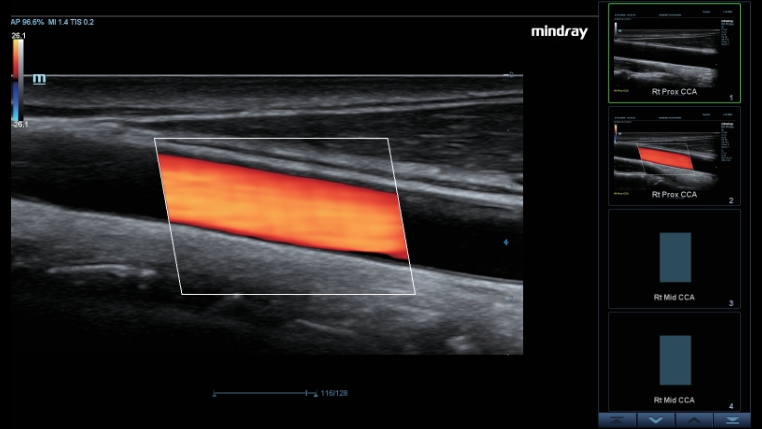

Transductores ComboWave

En comparaciĂłn con los sensores tradicionales, los transductores ComboWave utilizan un nuevo tipo de material piezoelĂ©ctrico compuesto que optimiza notablemente el espectro acĂșstico y reduce la impedancia acĂșstica. AdemĂĄs de integrarse con la tecnologĂa Ășnica 3T de Mindray, los transductores lineales ComboWave ofrecen un rendimiento sobresaliente con una gran resoluciĂłn de imagen y uniformidad en ecografĂas vasculares, de tiroides, de mama, etc.

Smart Track

Smart Track proporciona una optimizaciĂłn rĂĄpida e inteligente de imĂĄgenes vasculares con un sencillo manejo de un solo toque. Puede optimizar el espectro de Color, Potencia y PW mediante seguimiento automĂĄtico y reducir pasos que llevan tiempo. Por lo tanto, el flujo de trabajo del examen vascular se simplifica con una Ăłptima visualizaciĂłn.